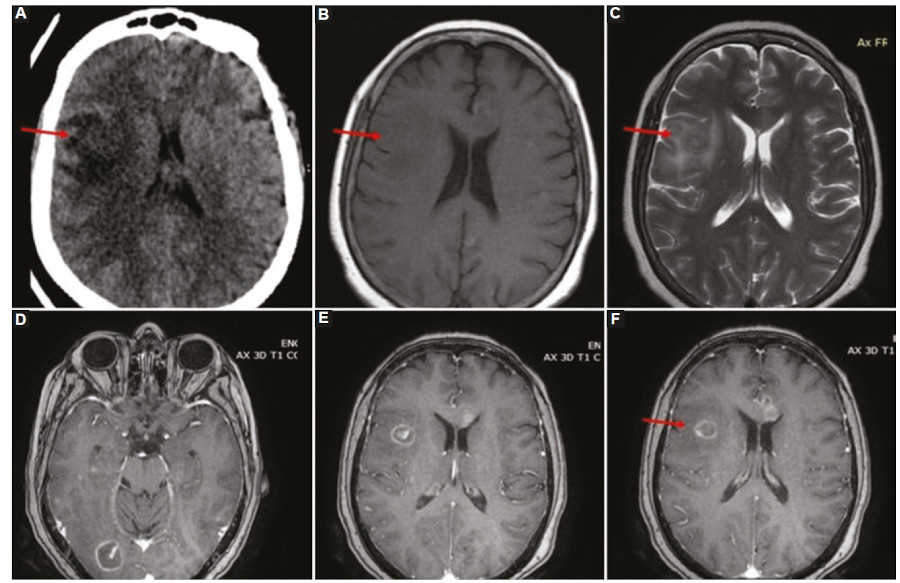

Las lesiones por SLPT del parénquima encefálico suelen ser masas corticales y subcorticales intraaxiales múltiples, con hemorragia, necrosis y edema perilesional, en general ubicadas en las estructuras supratentoriales más profundas, los ganglios basales, el tálamo y la región periventricular. Sin embargo, también pueden verse en el cerebelo y tronco encefálico48. Las lesiones tienden a infiltrar los tractos de sustancia blanca, incluido el cuerpo calloso y la cápsula interna. Las características de neuroimagen del SLPT son similares a las que se observan en personas inmunodeprimidas con linfoma primario del SNC11,48. En la TC, las lesiones parenquimatosas son isodensas-hiperdensas en relación con la corteza debido a su alta celularidad, característica que condiciona hipointensidad en secuencias ponderadas en T2 en la RM. Asimismo, con respecto a las demás secuencias de RM, las lesiones del SLPT se visualizan hipointensas o isointensas en secuencias ponderadas en T1, con áreas hiperintensas ocasionales que se deben a hemorragia intratumoral, con edema vasogénico peritumoral moderado. Ante la administración de contraste endovenoso se observa un patrón de realce en anillo similar al de un absceso cerebral en el 87% de los casos, o menos frecuentemente, con realce homogéneo, acompañado de edema vasogénico perilesional48) (Fig. 9).

Uno de los hallazgos característicos del SLPT del SNC es la marcada restricción en secuencias de difusión de la periferia de la lesión debido a la hipercelularidad, que corresponde a las áreas de realce periférico luego de la administración de gadolinio. Contrariamente a la apariencia de las lesiones de SLPT, los abscesos piógenos y, con menos frecuencia, los abscesos fúngicos pueden mostrar una difusión central restringida, ambos diagnósticos diferenciales del SLPT del SNC848.